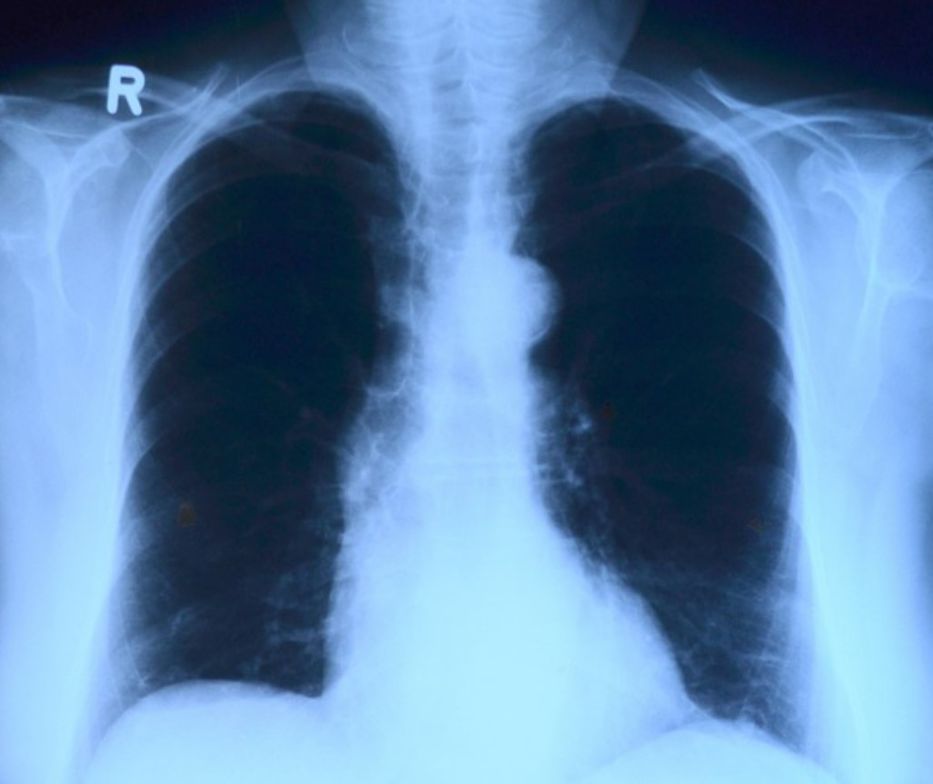

La contaminación del aire y las partículas vinculadas al cambio climático favorecen la aparición de cáncer de pulmón en personas no fumadoras, según una investigación presentada este sábado en el congreso que la Sociedad Europea de Oncología Médica (ESMO) celebra en París.

El estudio, elaborado por científicos del Francis Crick Institute and University College London, revela que las partículas que se encuentran en los tubos de escape de los vehículos y el humo de los combustibles fósiles promueven cambios cancerosos en las células de las vías respiratorias y generan más casos de cáncer de pulmón de células no pequeñas (NSCLC por sus siglas en inglés) entre la población que nunca ha fumado.

La investigación realizada sobre una muestra de medio millón de personas residentes en Inglaterra, Corea del Sur y Taiwán revela que la exposición a concentraciones crecientes de partículas suspendidas en el aire (PM2.5) está vinculado a un mayor riesgo de desarrollar cáncer de pulmón.